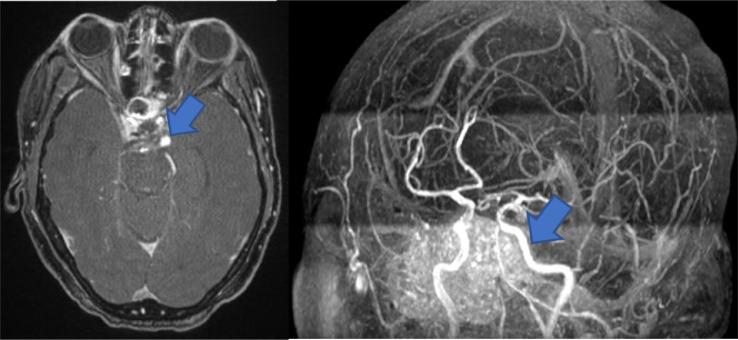

Cavernous internal carotid artery aneurysm presenting with ipsilateral oculomotor nerve palsy: A case report.

Internal carotid artery aneurysm with incomplete isolated oculomotor nerve palsy: a case report.